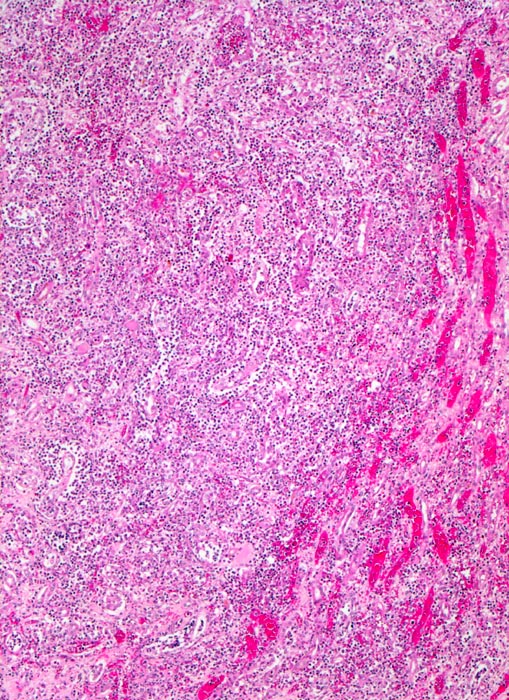

PathoPic – image database / PathoPic ID 4991 - akute Pyelonephritis (destruktive interstititelle Nephritis)

akute Pyelonephritis (destruktive interstititelle Nephritis)

Destruktives streifenförmiges granulozytäres Infiltrat. Die Tubuli sind nicht mehr erkennbar. Am Rand des Infiltrates hyperämische Gefässe (makroskopisch gelber Herd mit rotem Randsaum).

Uretero- und Nephrolithiasis

Fieber mit Schüttelfrost, Übelkeit und Flankenschmerzen. Dysurie. Exsiccose.